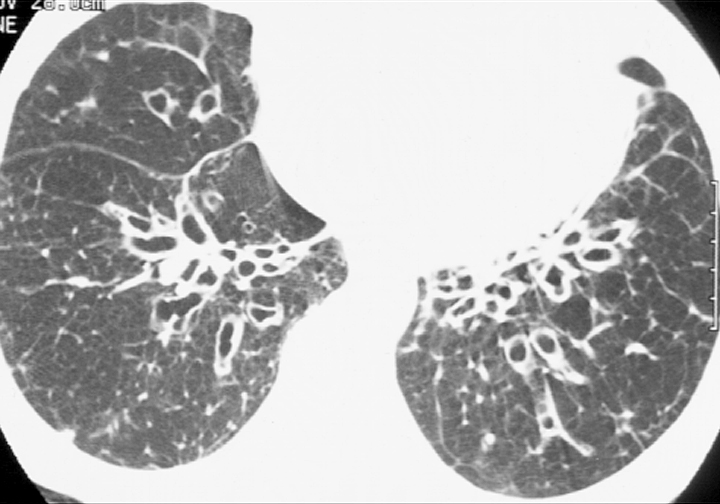

Bronchiectasis

Case 6 CT